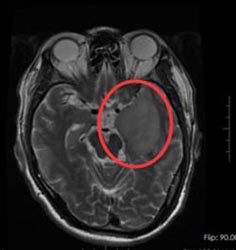

46岁的孙先生,半年前开始出现头疼、头晕症状,肢体活动正常,他觉得这是常有的小毛病,一直没有去医院。直到一周前,孙先生头痛症状加重,当地医院就诊,头部MRI提示左颞岛叶异常信号,考虑为低级别胶质瘤。

广东三九脑科医院进一步检查结果:1、左侧颞叶占位性病变;2、高血压病1级,高危组。

手术前